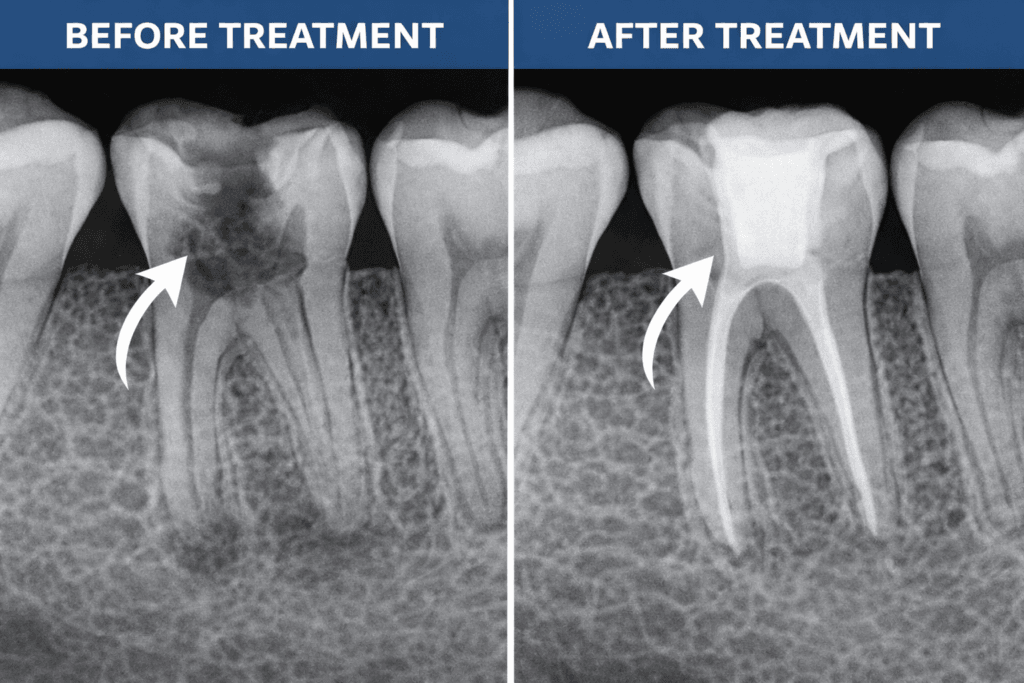

A root canal treatment can completely transform a damaged or infected tooth. Many patients worry about pain, appearance, and results before the procedure. Understanding root canal before and after results helps clear myths and sets the right expectations.

A root canal is a dental procedure used to remove infected or dead pulp from inside a tooth. After cleaning and disinfecting the canal, the dentist seals it to prevent further infection and restores the tooth with a filling or crown.

Dead tooth root canal before and after results are often dramatic, turning a failing tooth into a fully functional one.

Modern dental restorations make root-canal-treated teeth look almost identical to natural teeth.